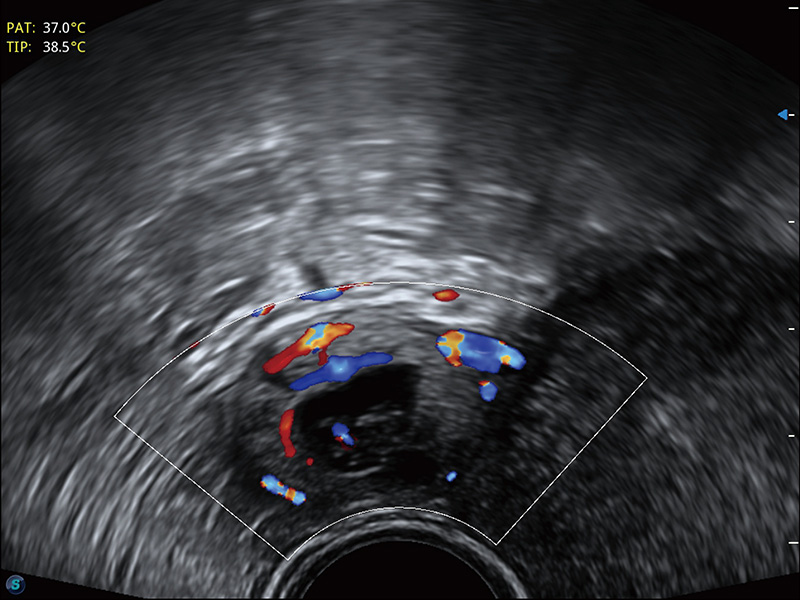

临床图

宫外孕血流